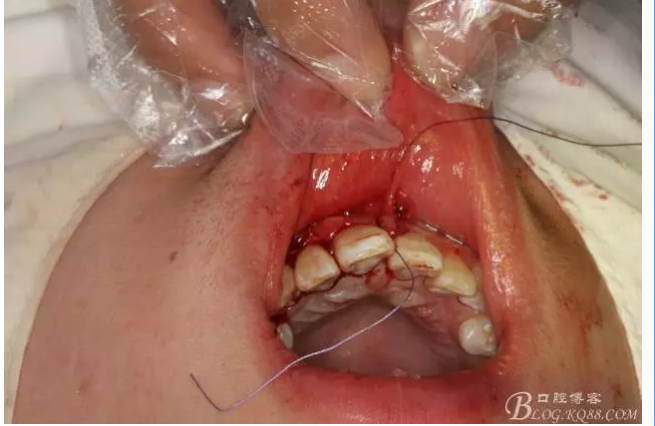

圖13.巨大骨腔填塞膠原蛋白海綿。

圖14.縫合水平切口

圖15.縫合垂直切口